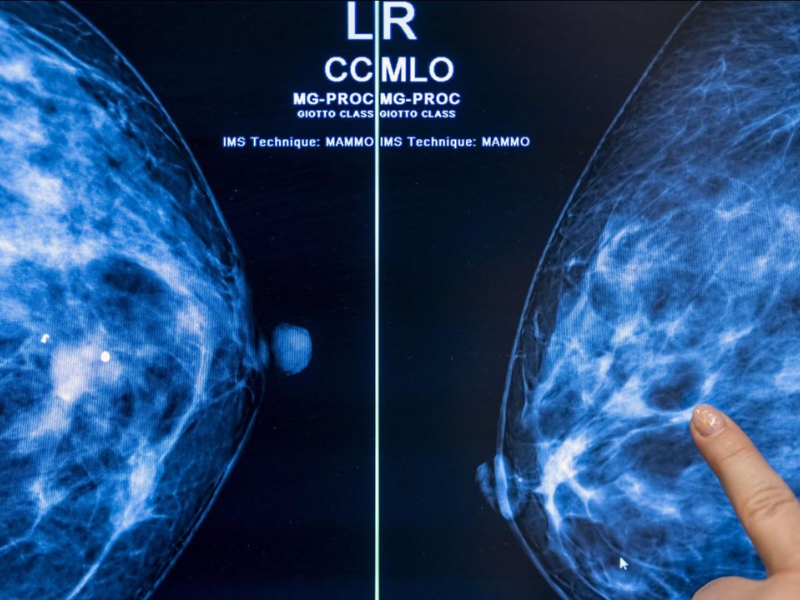

Cette avancée repose sur l’analyse automatisée d’images médicales. Parmi les solutions les plus avancées figure Clairity Breast, un système récemment autorisé par les autorités sanitaires américaines. L’outil a été entraîné sur environ 400.000 mammographies, ce qui lui permet d’identifier des signaux invisibles à l’œil humain.

Contrairement aux modèles classiques, qui combinent âge, historique médical et facteurs génétiques, cette technologie se base exclusivement sur l’image radiologique. L’algorithme analyse la densité mammaire, la texture du tissu et des motifs structurels complexes pour établir une probabilité de cancer à cinq ans.